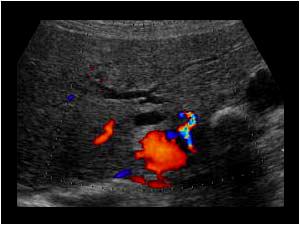

Mirizzi SYndrome

impacted stone in the cystic duct or GB neck

presence of two tubular structures representing the bile duct above the level of the cystic duct

Mirizzi SYndrome

impacted stone in the cystic duct or GB neck

presence of two tubular structures representing the bile duct above the level of the cystic duct